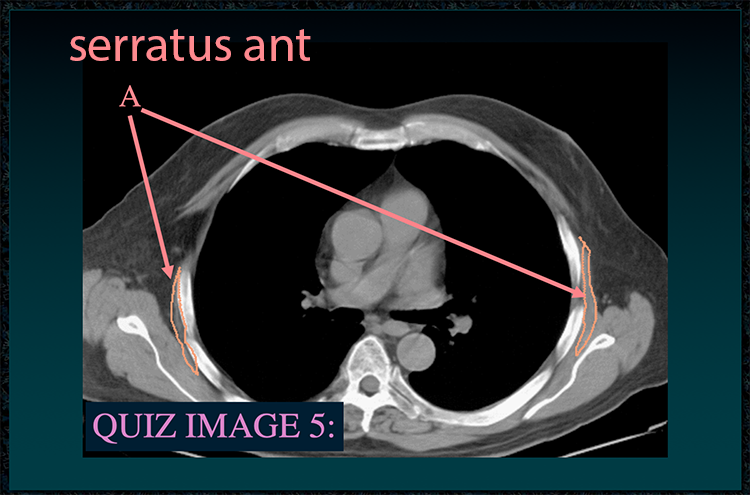

◂Chest Anatomy Review